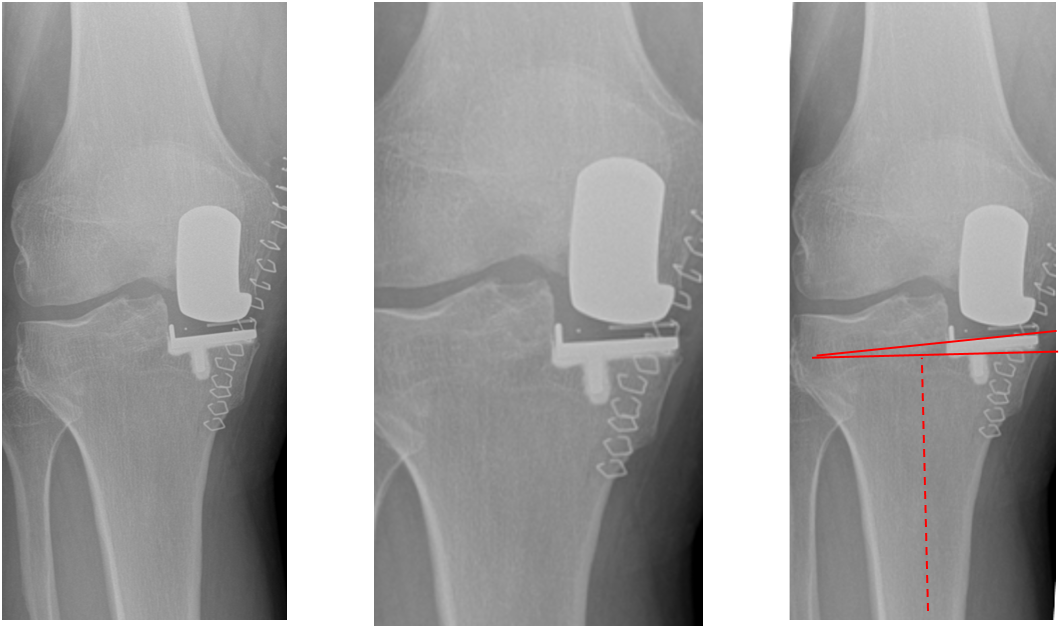

病例2:胫骨假体松动

病例2:单髁翻单髁

病例3:胫骨假体下沉

病例3:单髁翻单髁